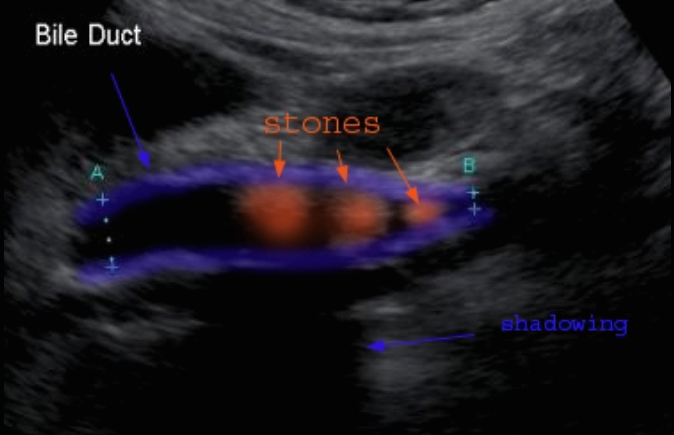

Choledocholithiasis US finding

- 총담관 내에 후방음향음영을 동반한 강한 에코가 관찰된다.

- 총담관의 확장 소견이 보인다. ( 7mm 이상)